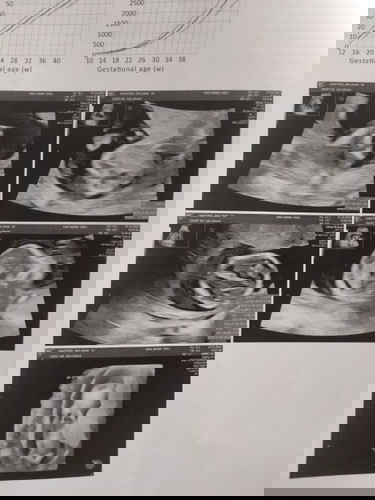

มีใครดูออกไหมคะ ว่าน้องหญิงหรือชาย คุณหมอบอกมอง ไม่เห็น 555 คุณแม่ก็ลุ้นไปจ้า

มองไม่เห็นเพศน้องค่ะ